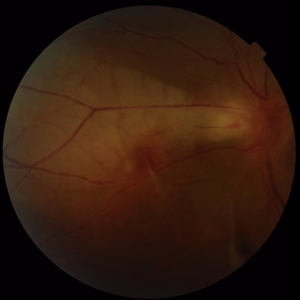

Best Disease Mar 9 2013 by Hamid Ahmadieh, MD Color fundus photograph the left eye of a 49-year-old man with decreased VA due to advanced Best disease. Photographer: Soodabeh Fooladin, Negah Eye Center, Tehran Condition/keywords: Best disease